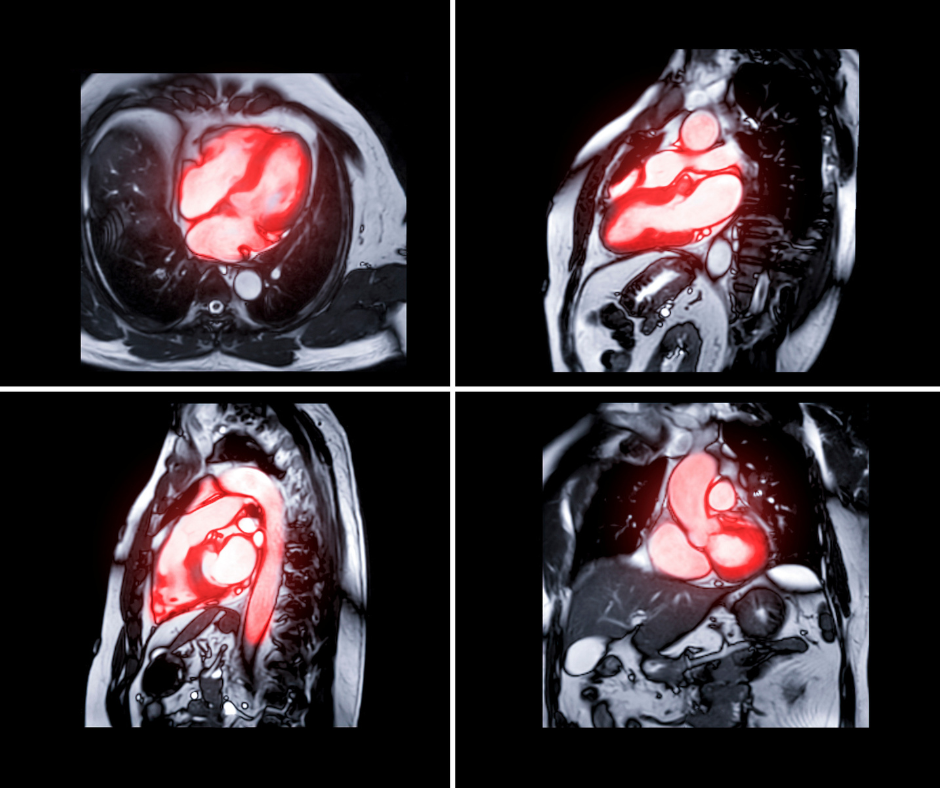

Figure 1 from MRIGuided Ventricular Tachycardia Ablation Integration Cardiac Defibrillator Mri a cardiac mri is a safe and painless test for most people. currently, about 8 million people worldwide are living with a cardiovascular implantable electronic device (cied) such as a. mri was considered dangerous for people with heart devices like pacemakers and defibrillators that were implanted after 2000,. the use of magnetic resonance imaging (mri) poses. Cardiac Defibrillator Mri.